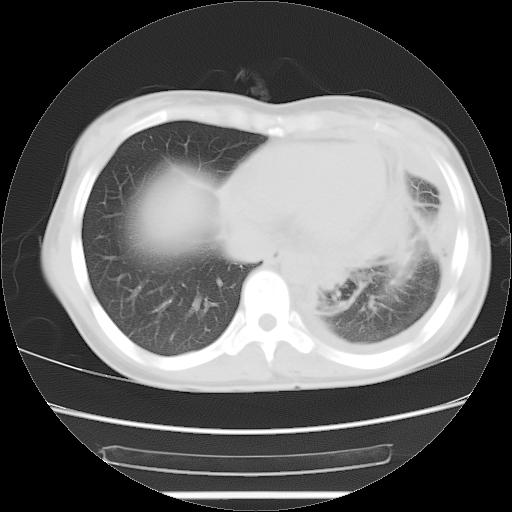

女,29岁,胸部不适,在外院胸片提示胸腔积液,到我院ct检查。

肺窗:

1、左侧包裹性积液伴叶间积液 2、右肺多发结节考虑增殖结节

左侧纵隔胸膜包裹性积液、左侧胸腔积液、胸膜肥厚粘莲,考虑结核性胸膜炎

左肺上叶不张,左侧胸水,叶间裂积液,纵隔淋巴结,脾脏钙化,考虑左肺上叶支气管内膜结核,结核性胸膜炎,脾结核

考虑:1.两肺tb;2.左侧胸膜炎、胸腔积液。

考虑两肺结核,左侧包裹性积液,叶间积液。

支持两肺继发性肺结核,左侧胸膜腔包裹性积液、胸膜肥厚,脾内多发钙化(结核钙化)。

右肺多发结节。左胸腔多发包裹性积液。